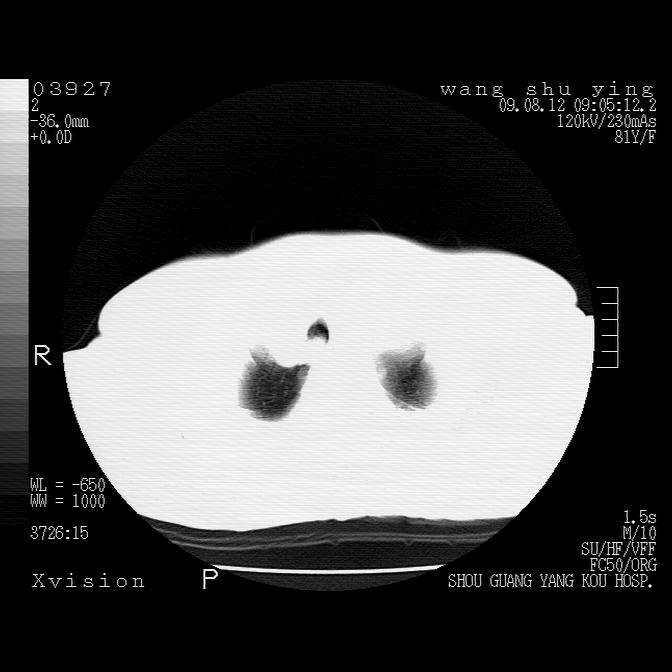

以下是引用帅河马在2009-8-12 12:59:00的发言:[br]两肺感染性病变伴双侧胸膜肥厚。[br]左侧甲状腺腺瘤不除外。[br]腹水+心包积液。[br][br][本贴已被 帅河马 于 2009-8-12 13:14:32 修改过]

以下是引用sdzyy在2009-8-12 18:17:00的发言:[br]两肺感染性病变伴双侧胸膜肥厚。[br]左侧甲状腺腺瘤不除外。[br]腹水+心包积液。[br]支持

以下是引用随光逐影在2009-8-12 19:42:00的发言:[br]1)两肺感染性病变伴双侧胸膜肥厚。2)不排除左侧甲状腺腺瘤。3)肝脏占位性病变;建议行进一步检查。